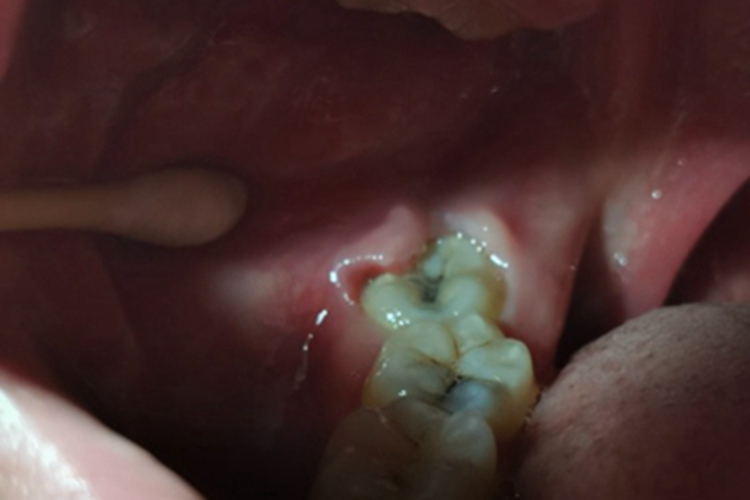

智齿冠周炎的损害可发生在牙龈,临床上可表现为患者的智齿上出现黑点,相邻的牙齿也有黑斑出现,龋齿已经形成。牙龈处发红发肿,局部化脓,且脓液增多,患者自觉有跳痛。